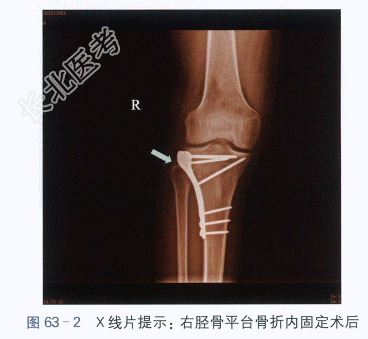

(2)X线片:右胫骨平台骨折术后,如图63-2所示。